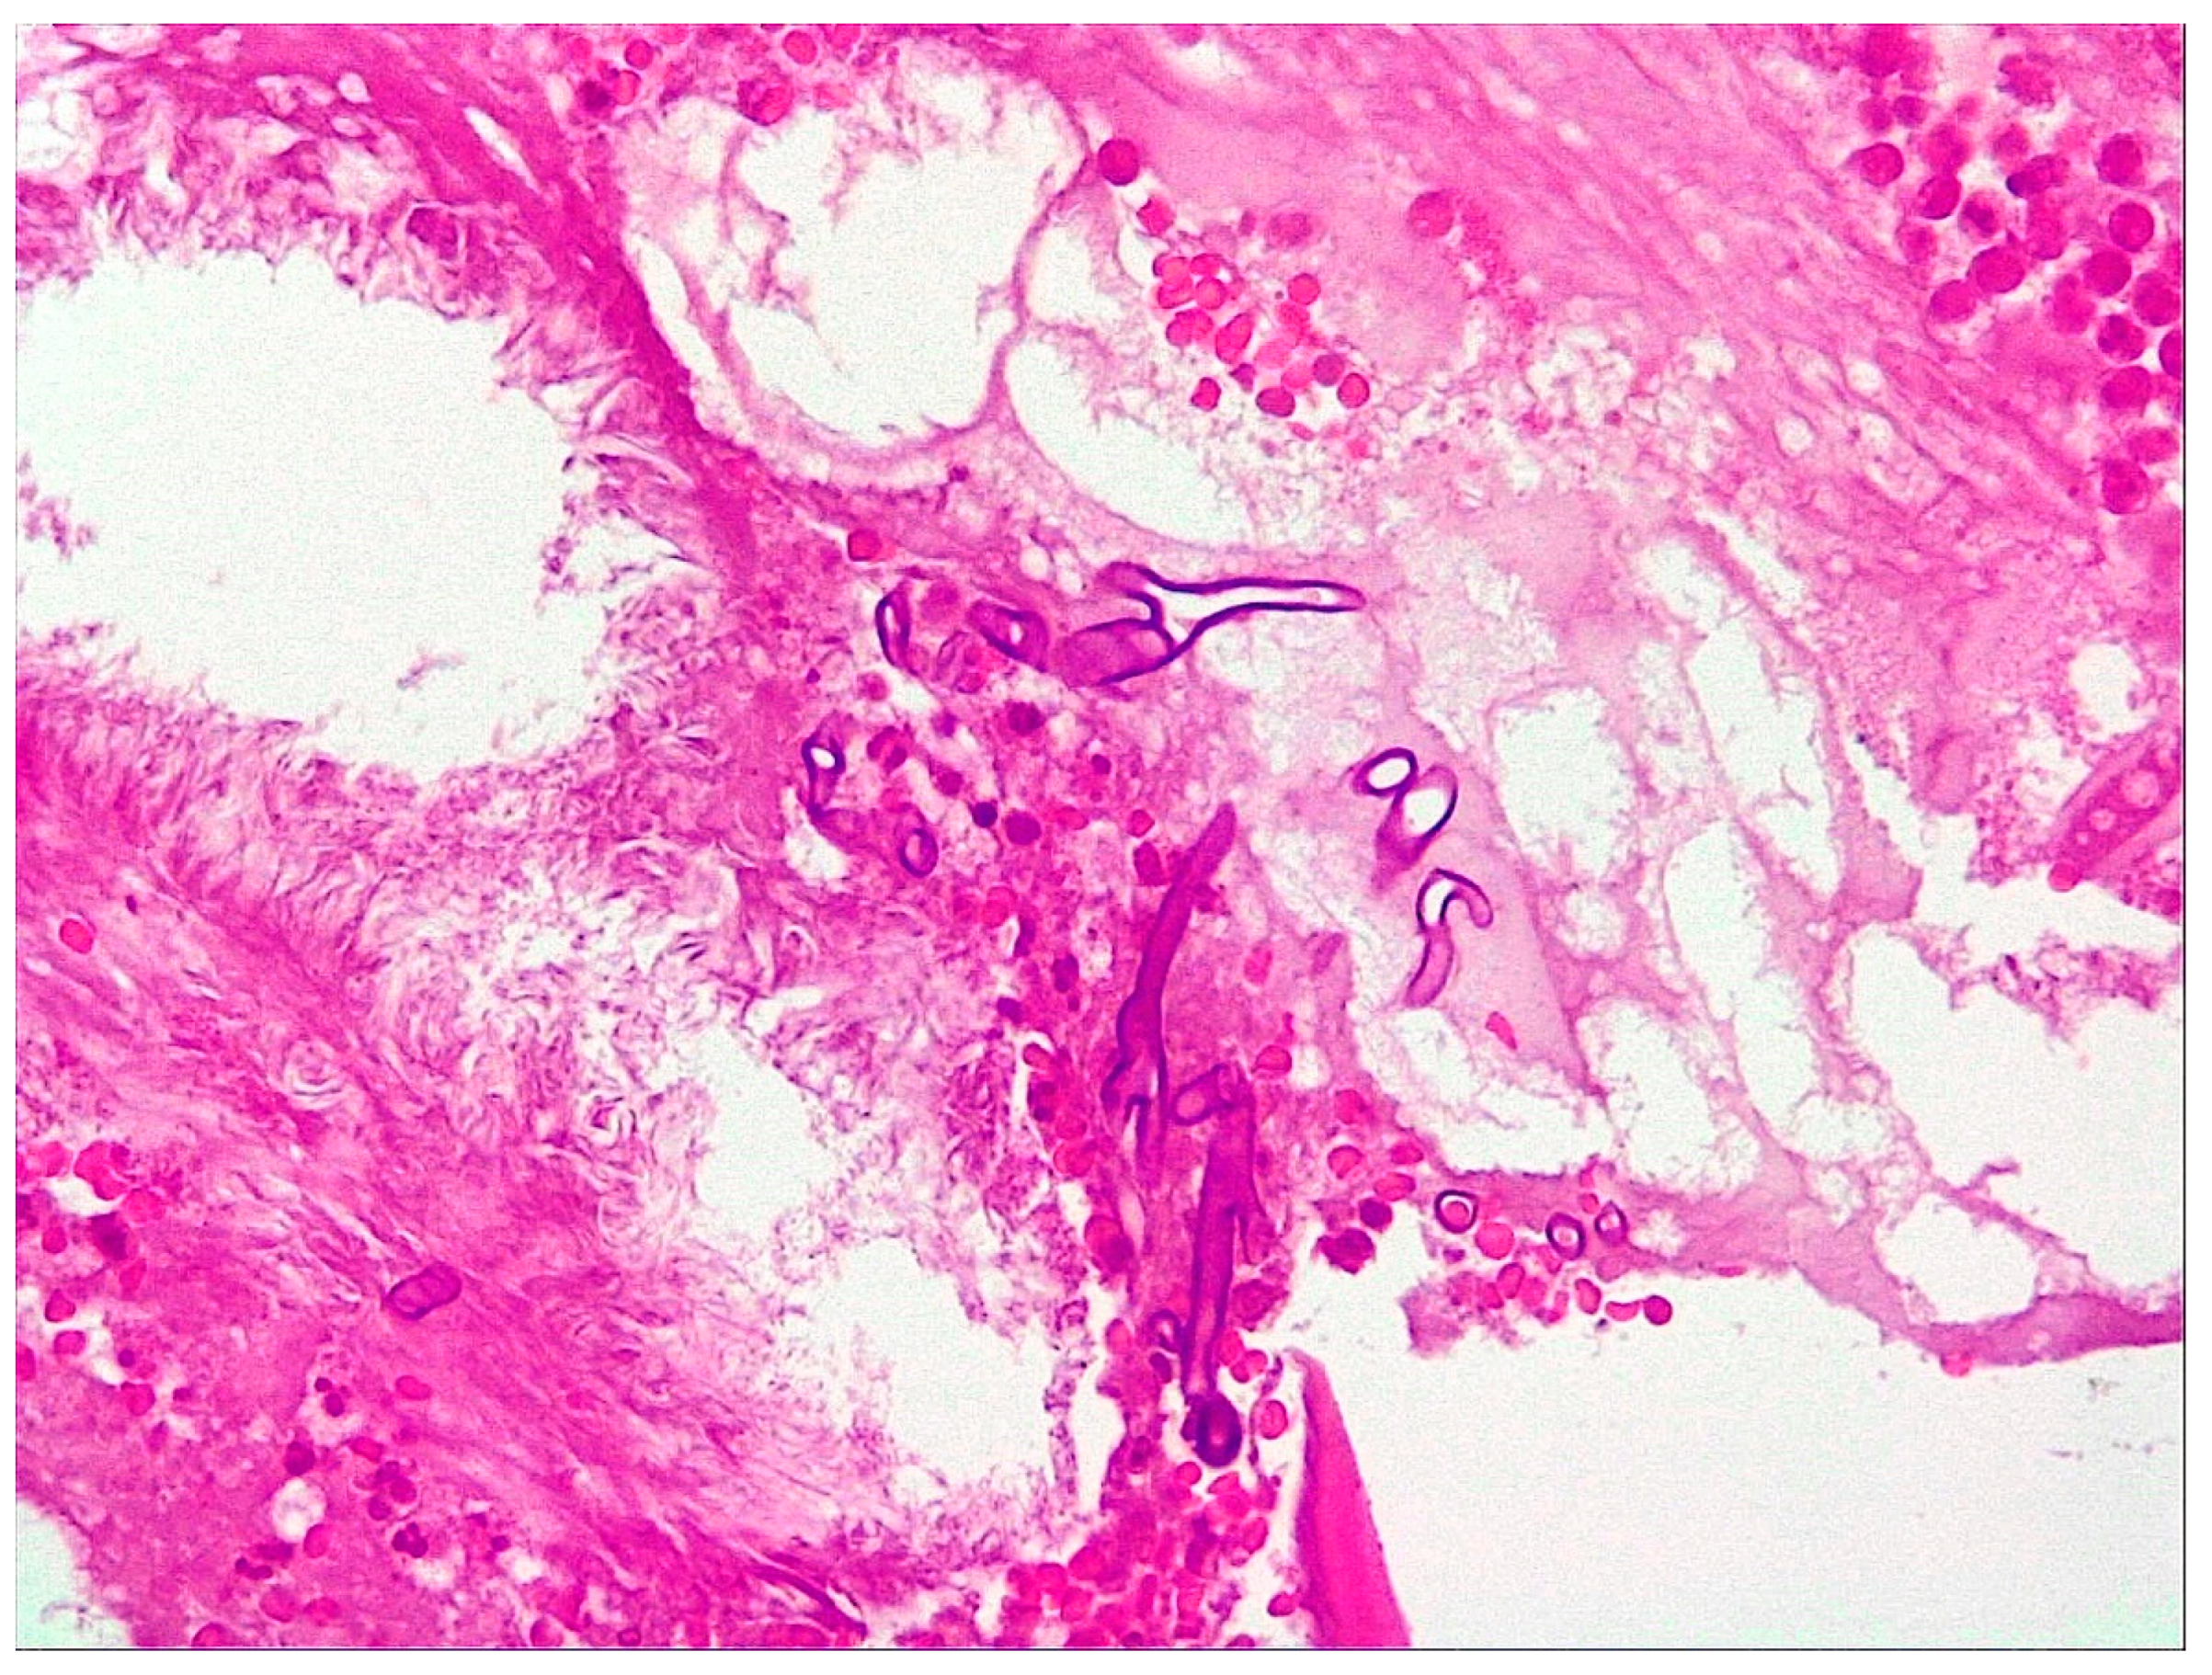

An 84-year-old female patient from an urban environment, known to have insulin-dependent type 2 diabetes mellitus, was admitted in August 2023 to the Ear, Nose and Throat (ENT) Department of the Bihor County Clinical Hospital, Romania, presenting with headache and swelling of the right eyelid. It is noteworthy that three weeks ago, the patient had a SARS-CoV-2 infection, which was managed at home (including moxifloxacin and dexamethasone, both for 10 days). On physical examination, she presented with necrosis of the mucosa and inferior nasal turbinate on the right side, with occasionally bloody and foul-smelling mucopurulent secretions, purulent endophthalmitis of the right eye, right eye blindness, and onychomycosis. A cranial CT scan revealed left orbital cellulitis with endophthalmitis, right pansinusitis with frontal, sphenoidal, and posterior ethmoidal collections, and adjacent bone lysis, Figure 5. Macroscopic histopathological examination revealed a black, foul-smelling crust lining the pituitary mucosa. The microscopic examination showed fragments with necrosis, inflammation, and hyphae in the form of thick ribbons measuring 10–20 microns, some of which were elongated. The microscopic appearance is suggestive of mucormycosis, Figure 6. Surgical treatment was initiated with the excision of necrotic tissues, antifungal therapy (posaconazole), hemostatics, and insulin. At the time of treatment, amphotericin B and isavuconazole were unavailable in the hospital. Laboratory tests showed elevated transaminases, prompting the addition of hepatoprotective agents, Table S2. The subsequent clinical course was favorable with posaconazole (for 6 weeks).

A 63-year-old male patient from a rural area was admitted to the ENT Department of Bihor County Clinical Hospital, Romania, in January 2022, complaining of headache, swelling of the left half of the face, and mucopurulent rhinorrhea. On physical examination, extensive necrosis of the left nasal cavity mucosa with black crusts and yellow-blackish secretions and a complete absence of the middle nasal turbinate were noted. The patient had a history of SARS-CoV-2 infection two months before onset (untreated with corticotherapy or antibiotics). A cranial CT scan revealed left pansinusitis with an extension of the inflammatory process to the left pterygoid musculature, Figure 7. Microscopic histopathological examination revealed non-septate hyphae angled at 90 degrees, along with areas of chronic inflammation and bacterial colonies, Figure 8. Periodic Acid-Schiff staining highlighted these hyphae, which were interpreted as mucormycosis. Surgical treatment was initiated with the debridement of necrotic areas, antifungal therapy (amphotericin B for 3 weeks), antibiotics (vancomycin, ciprofloxacin, both for 2 weeks), and analgesics, with favorable progress. On the 8th day of treatment, the patient developed acute renal failure (creatinine 4.98 mg/dL), prompting the discontinuation of vancomycin therapy to reduce nephrotoxicity, with subsequent favorable evolution and creatinine decreasing to 1.56 mg/dL, Table S3.

Figure 6. Microscopic examination of the biopsy specimen (400× magnification). Fragments with necrosis, inflammation, and hyphae in the form of thick ribbons measuring 10–20 microns and some elongated.

Figure 8. Microscopic examination of the biopsy specimen (400× magnification). Non-septate hyphae angled at 90 degrees, along with areas of chronic inflammation and bacterial colonies.